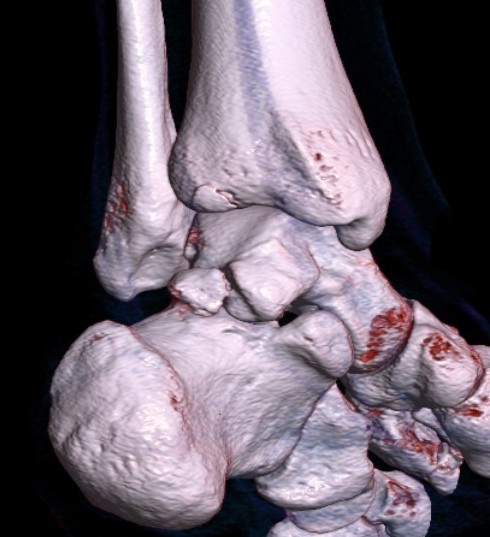

CT

Os trigonum

Fractured Stieda process

Os trigonum with osteochondral fracture posterior tibia